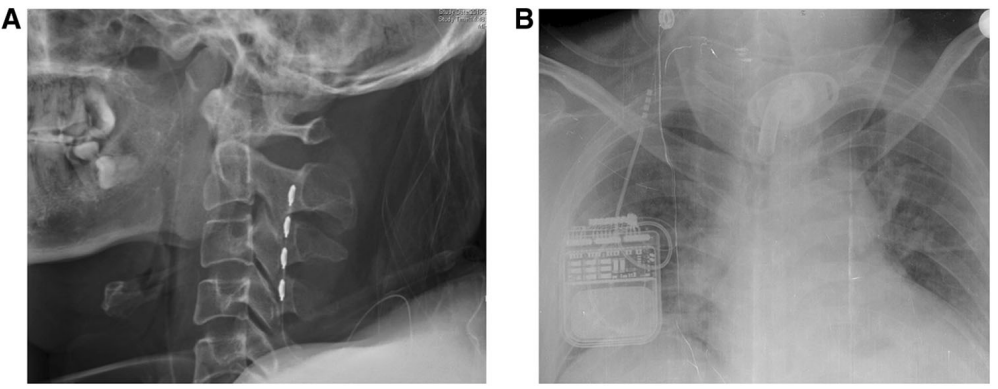

近年來(lái),SCS治療意識(shí)障礙得到越來(lái)越多的應(yīng)用。SCS通過(guò)手術(shù)放置刺激電極在頸髓C2-C4水平硬膜外正中部,電刺激通過(guò)上行性網(wǎng)狀結(jié)構(gòu)激活系統(tǒng)及丘腦下部激活系統(tǒng)傳達(dá)到大腦皮層。